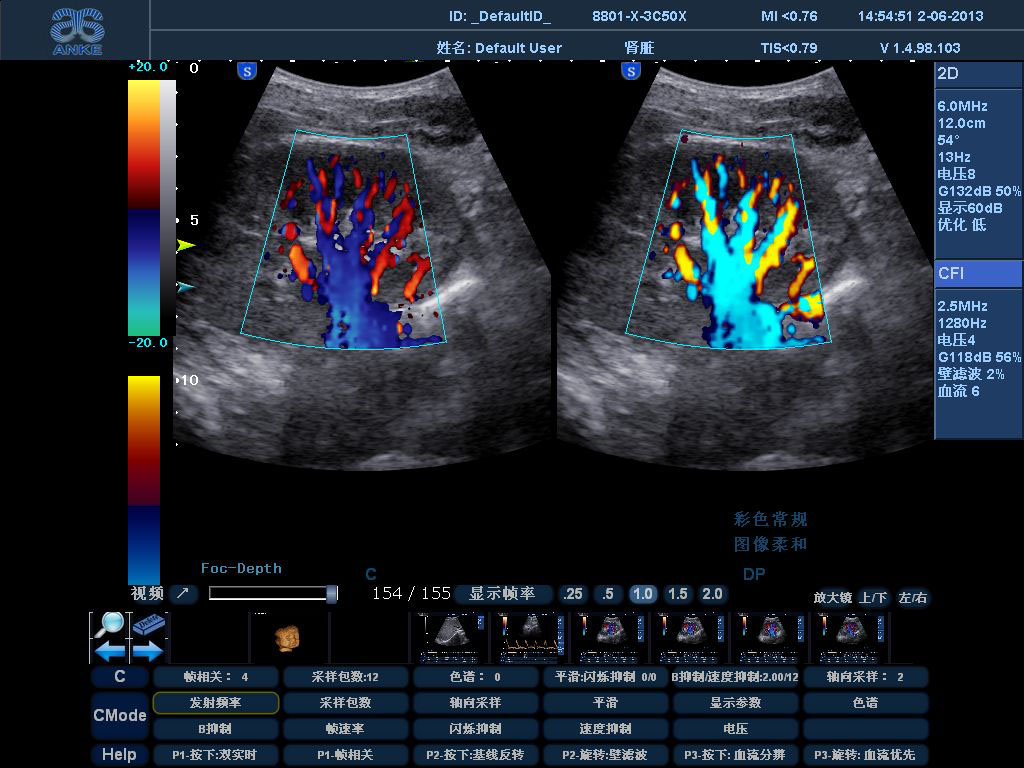

同时,B超也可作为其它超声诊断的基础,如D型超声,在B超的二维图像基础上增加了对血流的检测,可确定血管是否通畅,管腔是否狭窄、闭塞以及是否有病变。我们平时说的彩超,就是彩色多普勒超声检查。彩超在二维B超的基础上增加了血流情况的展示,根据血流的方向,屏幕上会呈现红色或蓝色,而组织、器官以及病灶仍以黑、白、灰的形式呈现。因此,彩超不仅可以评价组织、器官、病灶的二维结构,对血流情况也能较好的反映,从而对疾病的诊断更加全面直观。